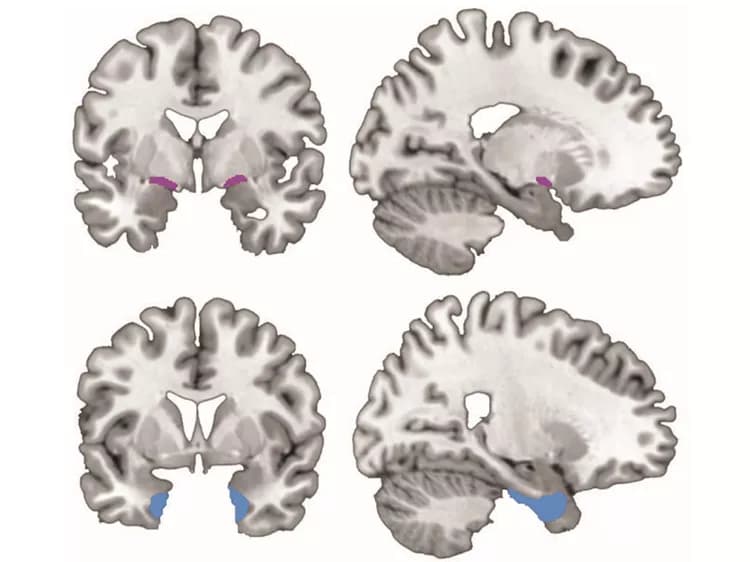

An international collaboration between Nathan Spreng, Cornell assistant professor of human development and the Rebecca Q. and James C. Morgan Sesquicentennial Faculty Fellow in the College of Human Ecology, and Taylor Schmitz of the University of Cambridge's Cognitive Brain Sciences Unit, sheds light on the basal forebrain region, where the degeneration of neural tissue caused by Alzheimer's disease appears even before cognitive and behavioral symptoms of the disease emerge.

The basal forebrain contains very large and densely connected neurons that are particularly vulnerable to the disease. Schmitz and Spreng show that, as Alzheimer's progresses, degeneration of the basal forebrain predicts subsequent degeneration in temporal lobe areas of the brain involved in memory. This pattern is consistent with other research showing that Alzheimer's indeed spreads across brain regions over time, but the study challenges a widely held belief that the disease originates in the temporal lobe.

Through analysis of high-resolution anatomical magnetic resonance imaging of brain volumes, taken three times over the two-year study period, the researchers were able to determine that individuals with MCI or Alzheimer's showed greater losses in gray matter volume in both the basal forebrain and temporal lobe, compared with cognitively normal controls. Intriguingly, they showed that over the two-year period, degeneration of neural tissue in the basal forebrain predicted subsequent tissue degeneration in the temporal lobe, but not the other way around.

A sampling of spinal fluid from healthy adults can detect an abnormal level of beta amyloid, indicative of Alzheimer's, Spreng said. Test results showed that temporal lobes looked the same regardless of amyloid level, but the basal forebrain showed notable degeneration among those seemingly healthy adults with abnormal amyloid levels.